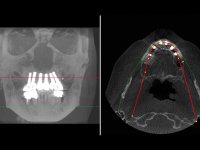

Realizada uma TAC, foi planificada a colocação de 6 implantes no maxilar superior. Foi decidida a colocação de dois implantes na zona dos incisivos centrais, dois implantes na zona dos caninos e dois na zona dos segundos pré-molares. A ausência de estrutura óssea na zona distal do primeiro quadrante implicava a realização de uma regeneração óssea no seio maxilar direito. A cirurgia foi realizada e após a colocação dos implantes foi feita a impressão para confeção de uma prótese provisória metalo-acrílica aparafusada para colocação em carga imediata no dia seguinte. O implante colocado na zona do seio maxilar direito não foi colocado em carga. Passados 6 meses foi realizada a impressão aos 6 implantes com técnica de moldeira aberta e foram confecionados os modelos de trabalho. Numa consulta seguinte foram montados os modelos de trabalho em articulador semi-ajustável utilizando o arco facial e a relação inter-maxilar obtida com a prótese provisória. Foi feita uma muralha de silicone sobre a ponte provisória com o objetivo de orientar o trabalho laboratorial. Realizada a infra estrutura metálica aparafusada esta foi provada em boca e finalmente após colocação de cerâmica o trabalho foi colocado definitivamente. Como passaram vários meses após a realização da primeira TAC foi feita uma segunda para planificar a colocação de implantes no 4º quadrante. Colocaram-se 3 implantes na mesma sessão em que foi feita a extração dos pilares da ponte. Estes implantes foram posteriormente reabilitados com uma ponte metalo-cerâmica aparafusada de três elementos.